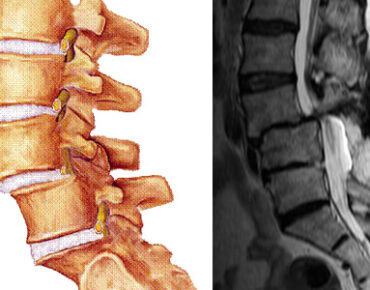

Ciddi bir omurga sorunu; spondilolistezis

Spondilolistezis (bel kayması), bir omurun bitişik omura g.